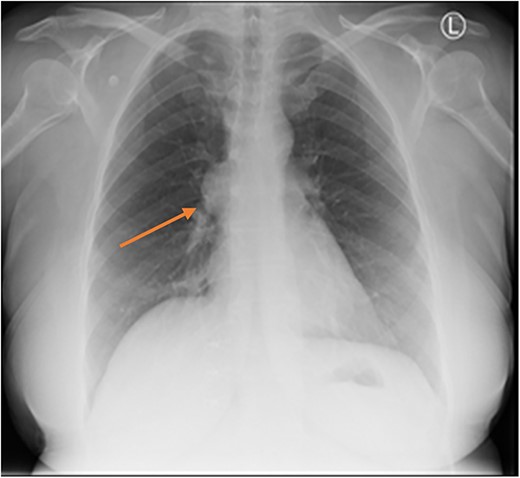

Three months later the patient re-presented with intermittent chest pain associated with a 2-day history of non-productive cough. She was investigated with a chest X-ray and then a contrast CT chest (Figs 1 and 2). Contrast CT chest demonstrated a 20 mm × 40 mm large, slightly lobulated, oval-shaped right anterior mediastinal mass placed more in the superior mediastinum (Fig. 2). The appearance suggested a cystic density within the patchy calcification in the capsule wall. The multidisciplinary team concluded the mass was a thymic or pericardial cyst and planned for surgical excision if there was any progression of the mass.